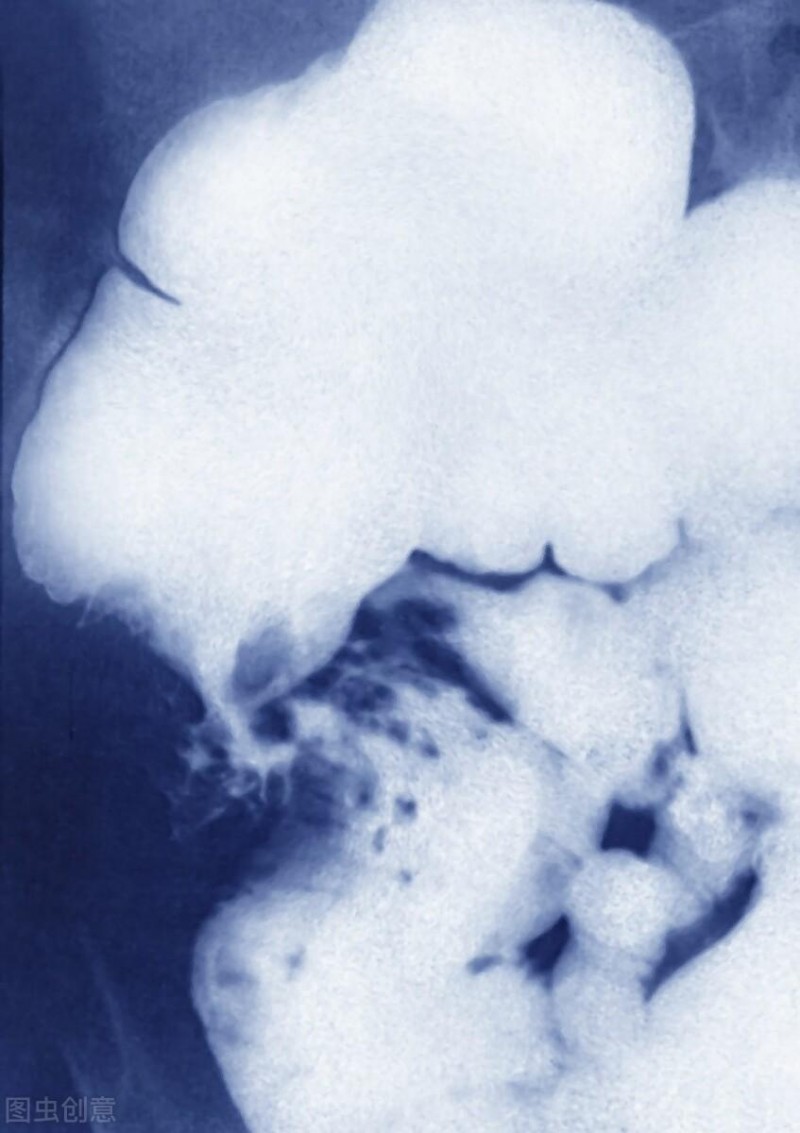

结直肠癌,一种可以保持沉默的癌症,结直肠癌早期可以没有任何症状出现,却是美国癌症有关死亡的第三大原因。3月份是结直肠癌月,您对于结直肠癌有足够的认识吗?结直肠癌早期没有任何症状,一经发现多数已为晚期。但是,筛查可以帮助早期发现癌症,可能涉及粪便检查、结肠镜检查或其他手术。无风险的普通人在50岁时也要开始进行结直肠癌筛查,但具有较高风险因素的人群,如克隆氏病